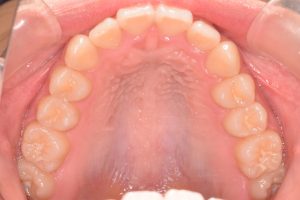

1期治療開始時(2024年3月)

2期治療開始時(2024年11月)

保定開始時(2025年1月)の写真です。

正面

上あご

下あご